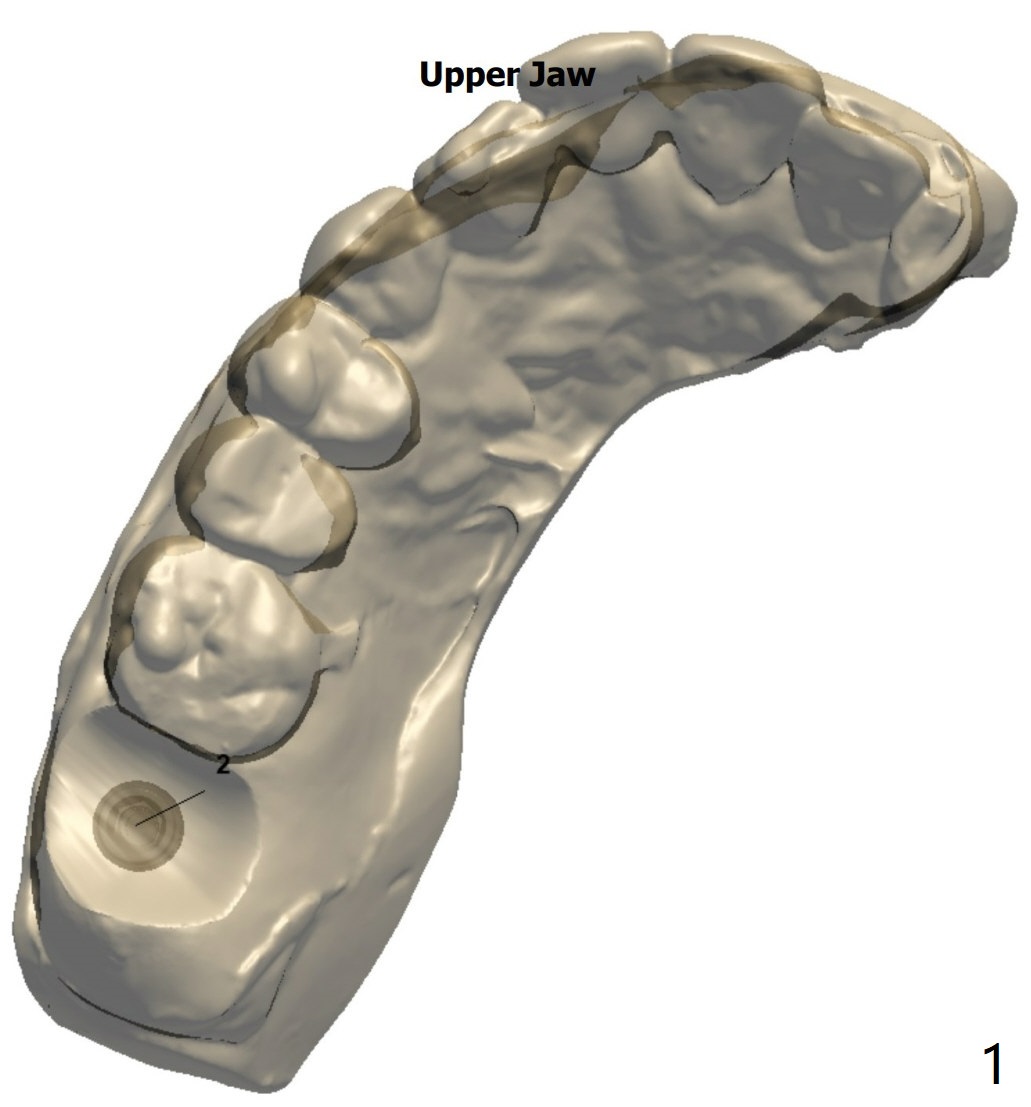

Mandatory Sinus Lift for #2

Return to Protect Graft